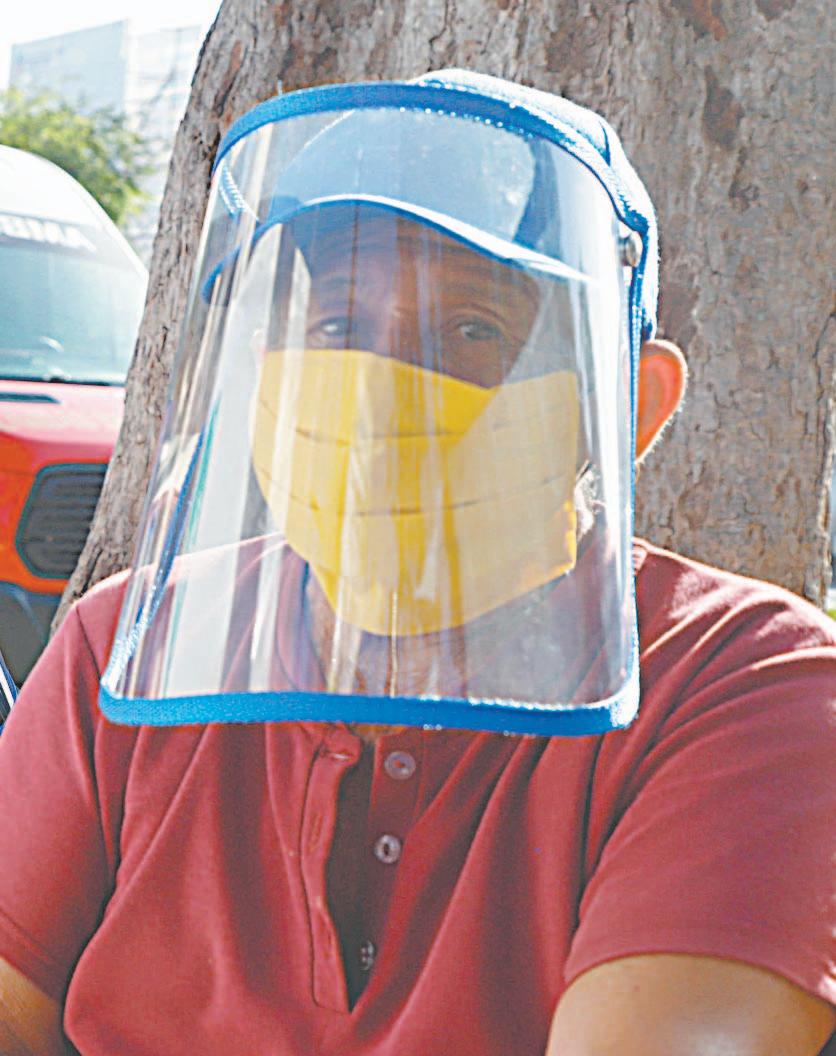

ya NO será obligatorio el uso de cubrebocas, salvo en instalaciones de salud y transporte público / La contaminación que causan granjas porcícolas, como Kekén, es un “asesinato a la Tierra”, alertan en la Cumbre SOS / Despido ilegal de 30 trabajadores le cuesta millonario embargo de bienes a Sindicato de Taxis, en Tizimín La Ciudad 3 y 5 / Municipios 17 EL Comité de Expertos de la Secretaría de Salud determinó que el Estado presenta datos favorables para la reactivación total; además del retiro de mascarillas, se dejará de emitir la información sobre el semáforo epidemiológico y se actualizarán las cifras del coronavirus cada 15 días.- (Martín Zetina) LA diputada federal Federica Quijano Tapia pidió llamar a cuentas a negocios porcícolas y avícolas que “solo ven por sus intereses”; Desarrollo Sustentable admite que “es una tarea pendiente”.- (POR ESTO!) COMO medida cautelar por una demanda de exempleados, un juez ordenó asegurar 11.7 millones de pesos, siete propiedades y cheques a una organización transportista del Oriente del Estado.- (POR ESTO!)

Yucatán dice adiós al cubrebocas

A partir del lunes, el uso solo será obligatorio en instalaciones de salud y transporte público

La Secretaría de Salud del Estado (SSY) informó que, a partir del próximo lunes 26 de septiembre, el uso de cubrebocas será voluntario, con excepción de hospitales, centros de salud, unidades médicas y transporte público, donde continuará siendo obligatorio.

La medida, informó la dependencia, obedece a la reducción en el número de contagios y fallecimientos por coronavirus, “resultado del trabajo en equipo que sociedad y Gobierno han realizado en Yucatán”.

Además, se dejará de emitir el Semáforo Epidemiológico Estatal, que se encuentra en color verde, y las cifras sobre el comportamiento del COVID-19 se actualizarán cada 15 días en la página electrónica de la dependencia estatal.

Las medidas se acordaron en una reunión del Comité de Expertos, integrado por especialistas yucatecos en salud pública y privada, y el titular de la SSY, Mauricio Sauri Vivas; ahí, se reportó que, actualmente, el Estado presenta datos favorables para dar un paso más a la reactivación total.

La obligatoriedad del cubrebocas se ha ido restringiendo no solo en México sino también en el extranjero. Hace unos días, Hugo López-Gatell, subsecretario de Prevención y Promoción de la Salud, señaló: “En este momento, con índices de contagio mínimos, posiblemente los menores que hemos tenido, no sólo en México, sino en general en el mundo, el cubrebocas es aun de menor utilidad”.

Incluso, remarcó que “la ma-

yor utilidad del cubrebocas es en espacios públicos cerrados en donde no se puede conservar una sana distancia, una distancia adecuada entre personas. En el transporte público, sobre todo el terrestre, puede seguir siendo de utilidad, y la utilidad depende, desde luego, de qué tantas personas pudieran estar infectadas”.

En Yucatán, el pasado 12 de mayo se dispuso el uso voluntario del cubrebocas en espacios abiertos, pero se mantuvo como obligatorio en lugares cerrados, así como en el transporte público; también se retiró la obligatoriedad de filtros sanitarios a la entrada de cada lugar y se mantuvo en escuelas; de hecho, este “control de Salud” a la entrada de los planteles educativos de Yucatán también se mantiene como obligatorio.

A pesar de la “liberación” del uso obligatorio de mascarillas quirúrgicas, la SSY recomienda, a manera de prevención, continuar

con esta medida en ancianos, personas con comorbilidades que ponen en riesgo su salud o síntomas de alguna enfermedad respiratoria.

No obstante los significativos avances frente al coronavirus, el Comité de Expertos y el funcionario estatal reiteraron el llamado a la población yucateca a actuar con mucha responsabilidad y mantener los hábitos sanitarios básicos, ya que, de registrarse algún repunte importante en los casos, se podría retomar algunas medidas para proteger la salud de los yucatecos.

La obligatoriedad de la mascarilla se ha ido restringiendo en varias partes del mundo. (Daniel Silva)

En instalaciones de salud del Estado, la protección es forzosa.